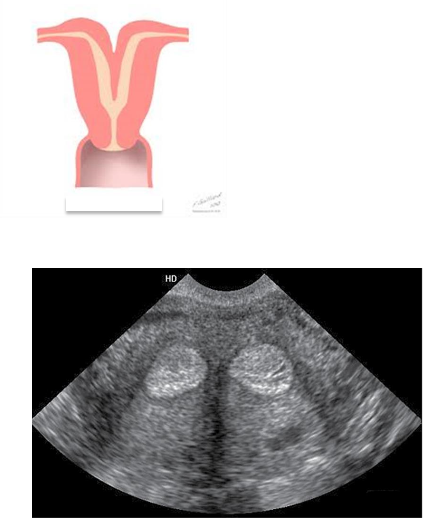

– Improper fusion leads to two partially or completely separate bicornuate uterine cavities.

– The uterus is heart-shaped

– Most common congenital uterine anomaly.

Bicornuate uterus

This is?

Bicornuate Uterus